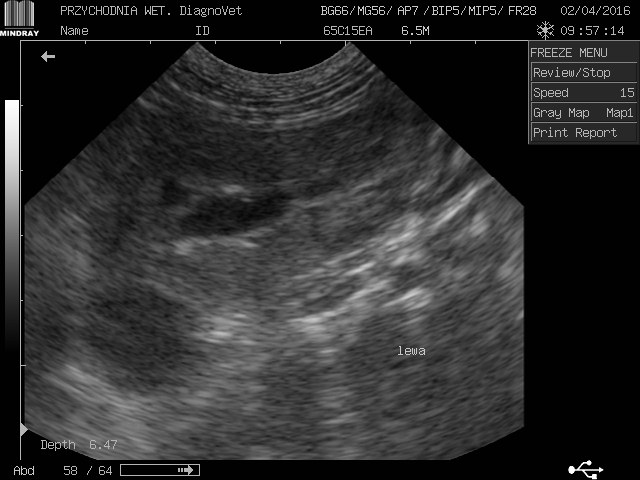

gracja1 Posted August 24, 2017 Posted August 24, 2017 Witam moja ukochana psinka gracja z wyników usg jest w bardzo kiepskim stanie nerki a praktycznie ich brak kwalifikują ja tylko do eutanazji jeżdżę od weta do weta i wszędzie żadnej pomocy.Gracja to piesek mieszany średniej wielkości trafiła do nas w ubiegłym roku ma zaledwie 2 lata.O chorych nerkach dowiedzieliśmy sie tydzień po przyjeździe jak do nas trafiła od początku objawy były ciągłe pragnienie wody i częstomocz decyzja tylko jedna jedziemy do weterynarza tam stwierdzono ze to zwykłe przeziębienie minęło parę dni brak poprawy u pieska powrót do weterynarza.Kazano zrobić badanie krwi moczu i wyszło kreatynina i mocznik podwyższony skierowano mnie na badanie usg tam potwierdziło chore nerki liczne cysty wokół diagnoza eutanazja natychmiastowa.Nie poddałam się minął rok z gracja od tamtej pory jest zemną bawi się biega kocha mnie nad życie lecz od paru dni dziwnie zaczęła się zachowywać jest osowiała mało zjada pije wodę wzięłam ja do weterynarza po diagnozie weterynarze są w szoku ze moja gracja żyję a na wieść o tym we dwoje zaczęli usg i to co zobaczyli to praktycznie brak nerek jedynie cysty do tej pory niewiadomo co tak naprawdę trzyma psa przy życiu i dziwią się ze on chodzi i biega w takim stanie a ja słyszę tylko w kółko pies do usypania zero szans zero leków absolutnie żadnej inicjatywy ze strony lekarza czy to normalnie dlatego jestem tutaj i opisuje swoja sytuacje a gracja leży przy mnie i nikt niepotrafi pomóc.Przesyłam skan usg krótko po przyjeździe gracji do mnie i pierwsze usg proszę o jakieś wskazówki do kogo jechać z kim porozmawiać bo siedzę i tony łez wylewam.Wyniki krwi z dnia 22.08.2017 Kreatynina 8.70mg/dl ,mocznik 300mg/dl 1 Quote